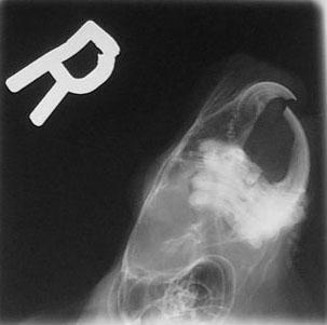

Below are x-rays of both a normal chinchilla and a chinchilla with malocclusion.

Maloccluded

The maloccluded x-ray shows overgrowth of both the roots and the crowns. There is no clear line where the upper and lower teeth meet. Also, the roots are growing both out of the lower jaw and into the eye sockets.